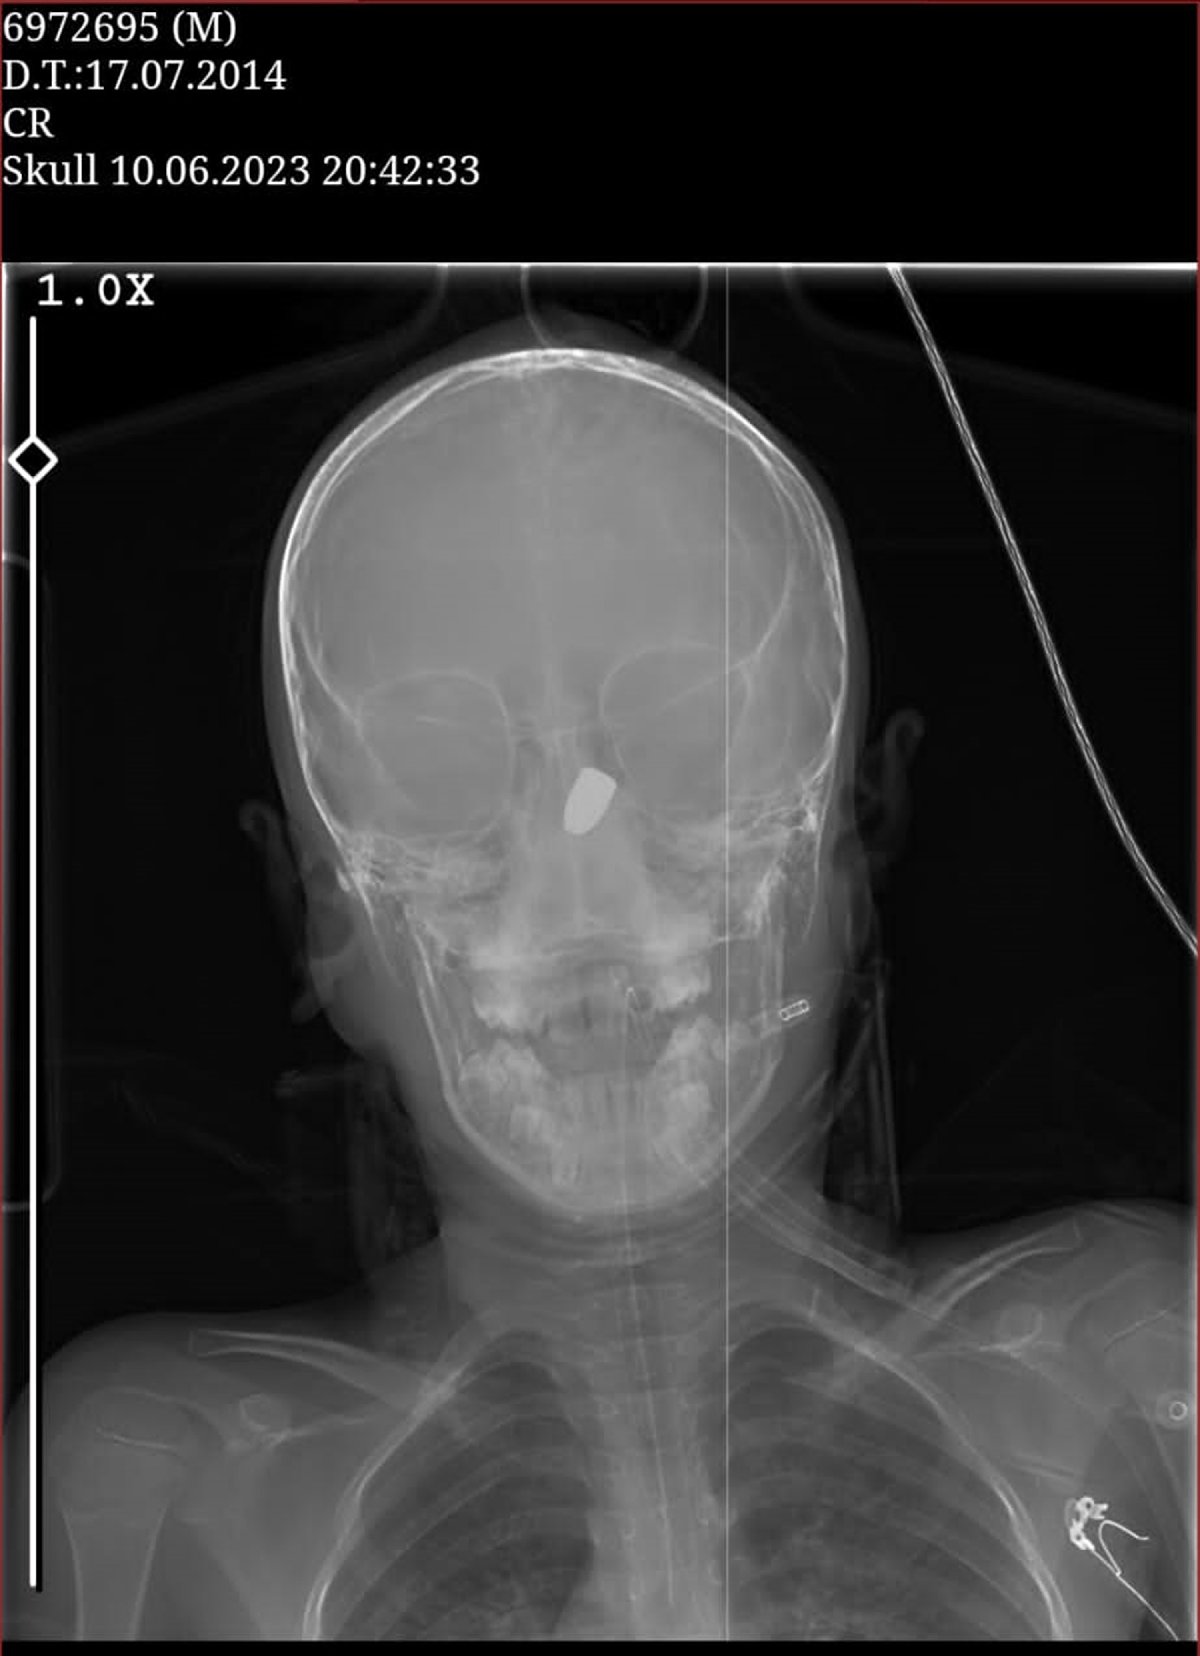

Sağlık ekipleri tarafından KTÜ Farabi Hastanesi'ne kaldırılan Özdemir'in yapılan tomografisinde başına yorgun mermi isabet ettiği belirlendi. Mermi çekirdeği beyninin 6 santimetre derinine saplanmış ve risk oluşturduğu için küçük çocuğa ameliyat yapılamamıştı. Bu nedenle 9 yaşındaki Özdemir yoğun bakım servisinde tedavi görmeye devam etti.